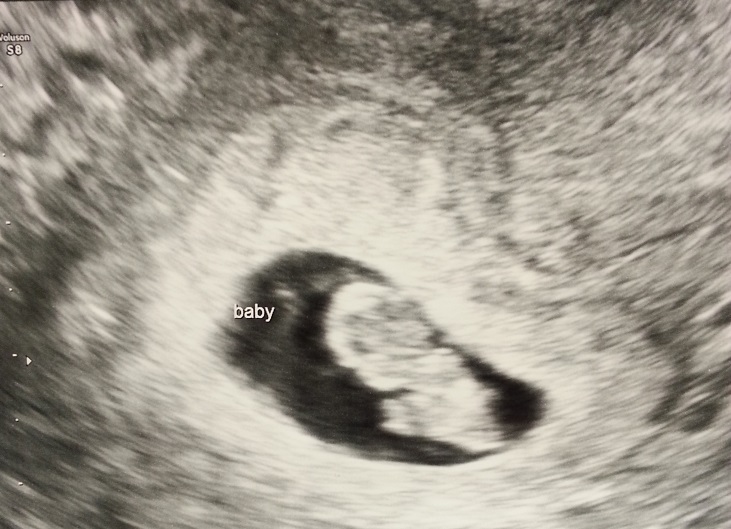

I love u/s pics!! Here is mine from last week @ 8w2d. 167 heartbeat. The tech labeled him/her baby, as you can see...... just in case I wasn't sure what I was looking at! :>